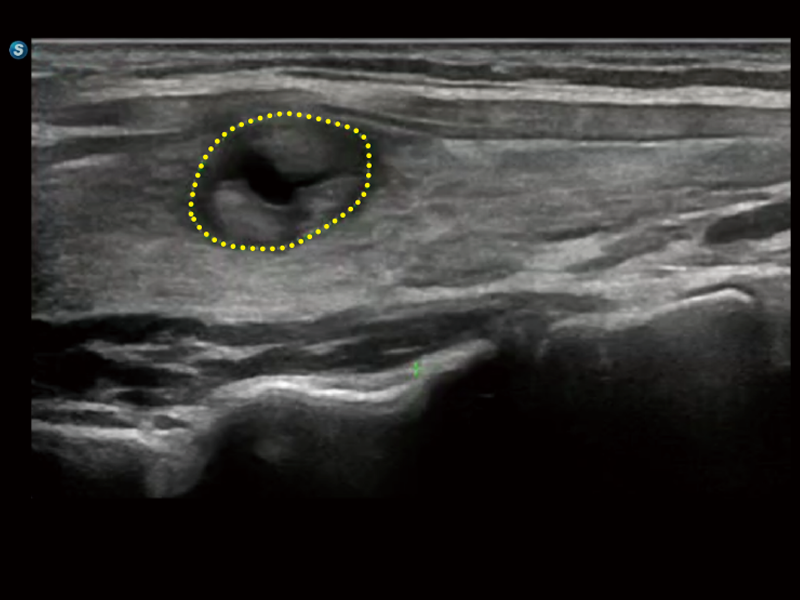

作为开立医疗全新打造的超高端旗舰超声产品,从探头抬起唤醒开启扫查到多维探头发射接收,通过先进的场成像发射、自适应聚合重建等技术,基于RF Data原始射频数据在图像生成、高端功能等方面实现突破,提供多科室综合临床解决方案。

独有场成像发射技术

自适应聚合重建技术